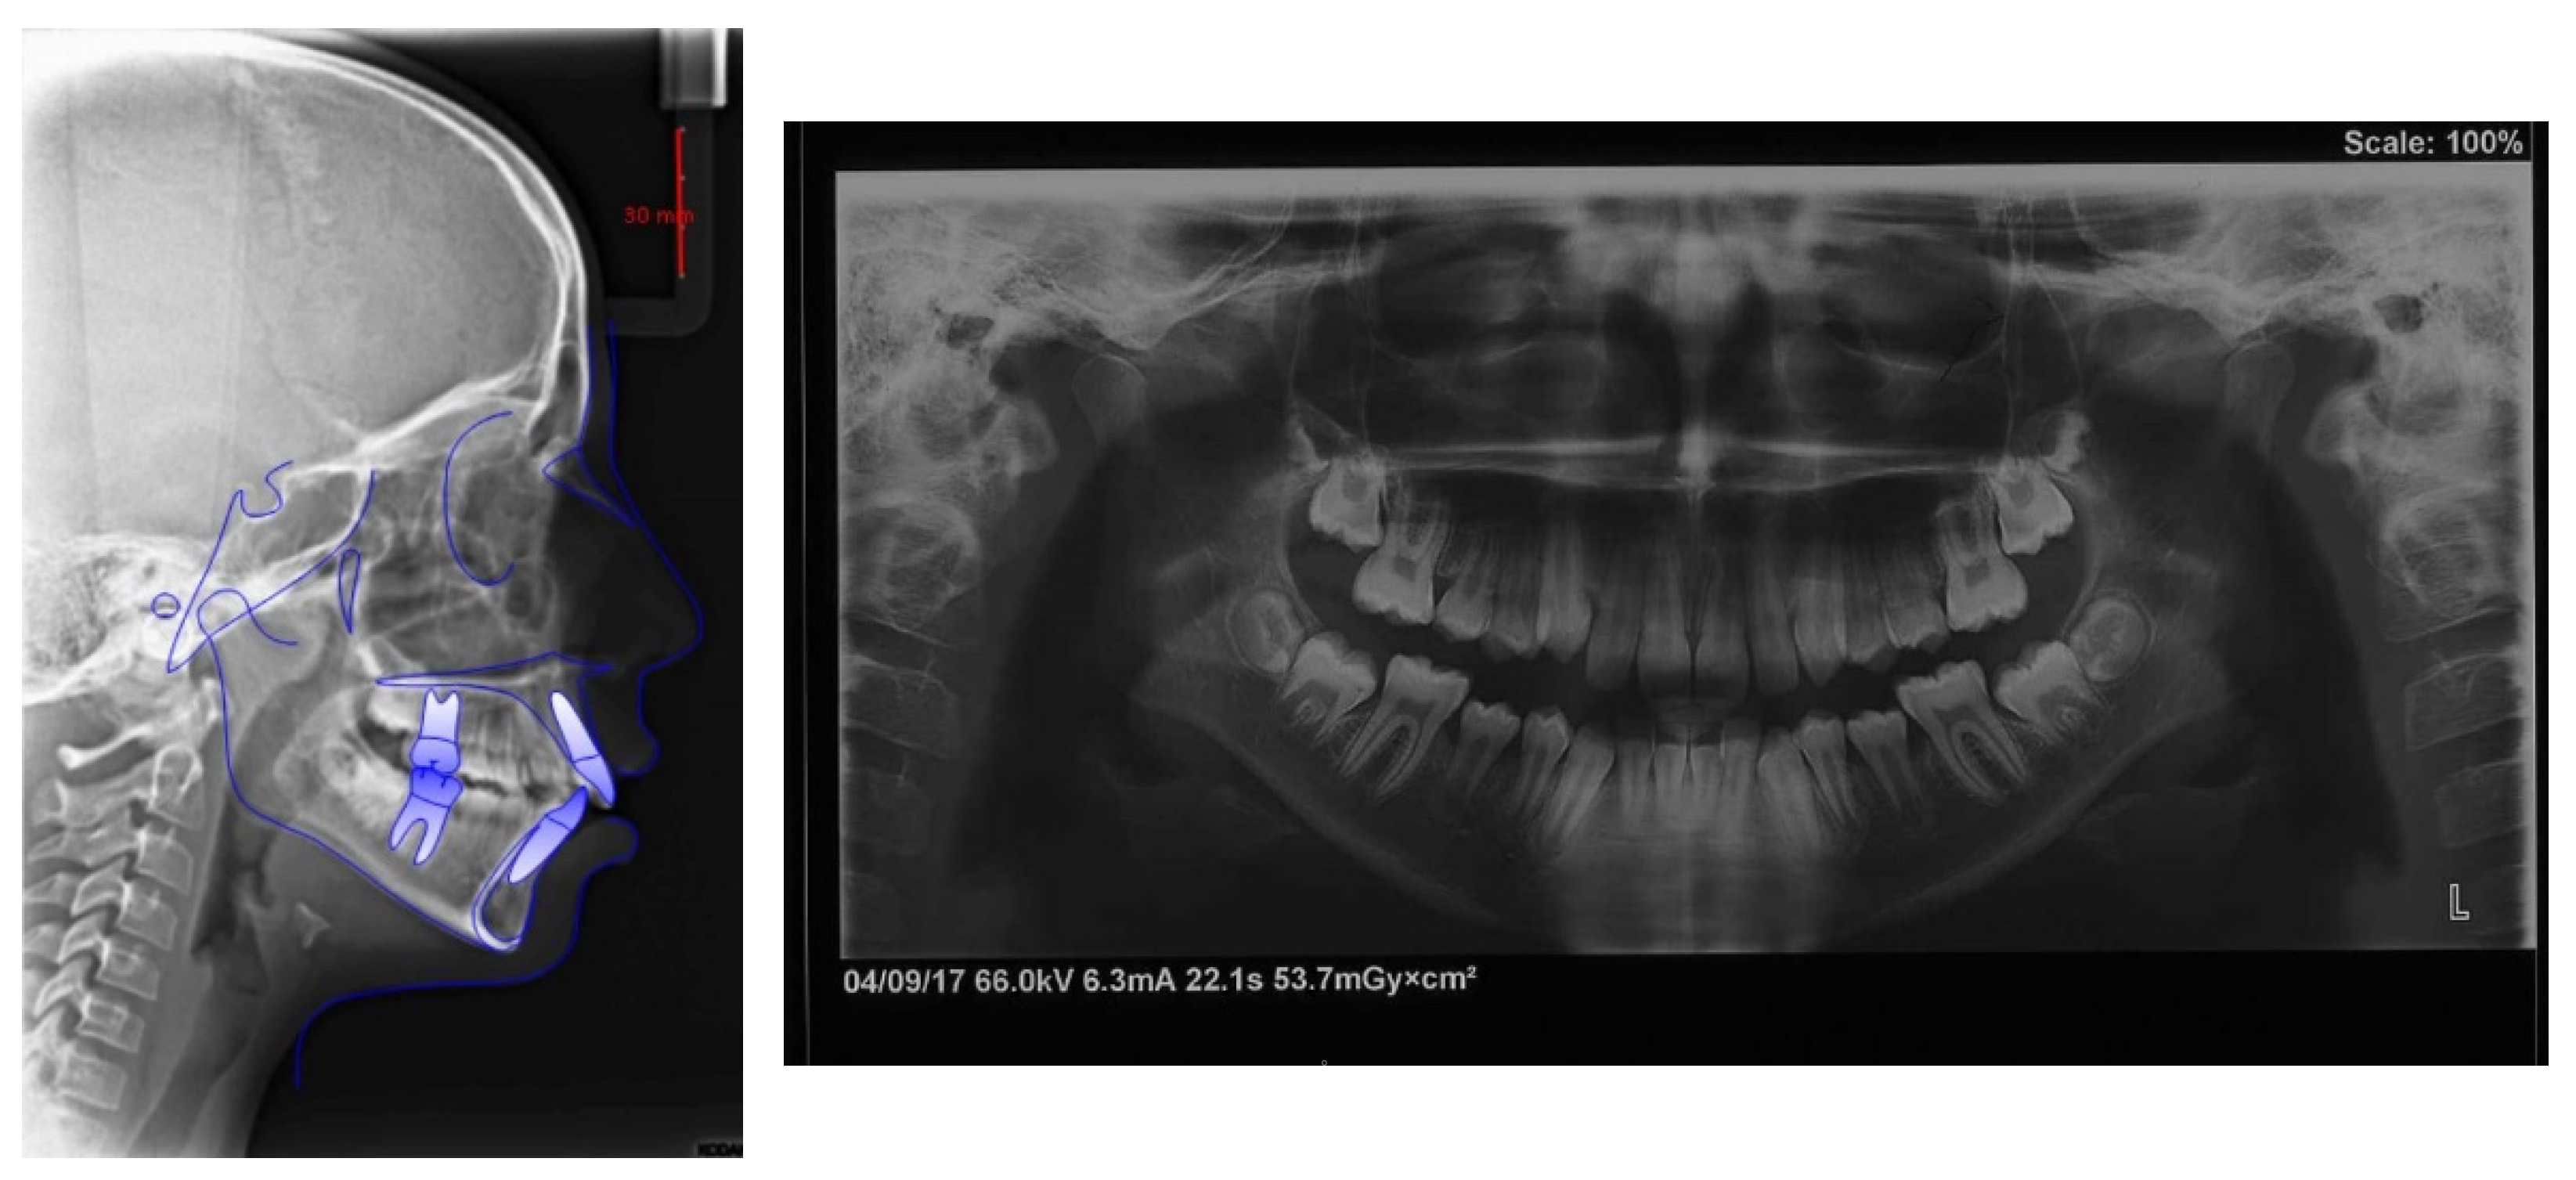

4.1. Etiology and Diagnosis

4.2. Treatment Objectives

4.3. Treatment Strategy

4.4. Treatment Progress